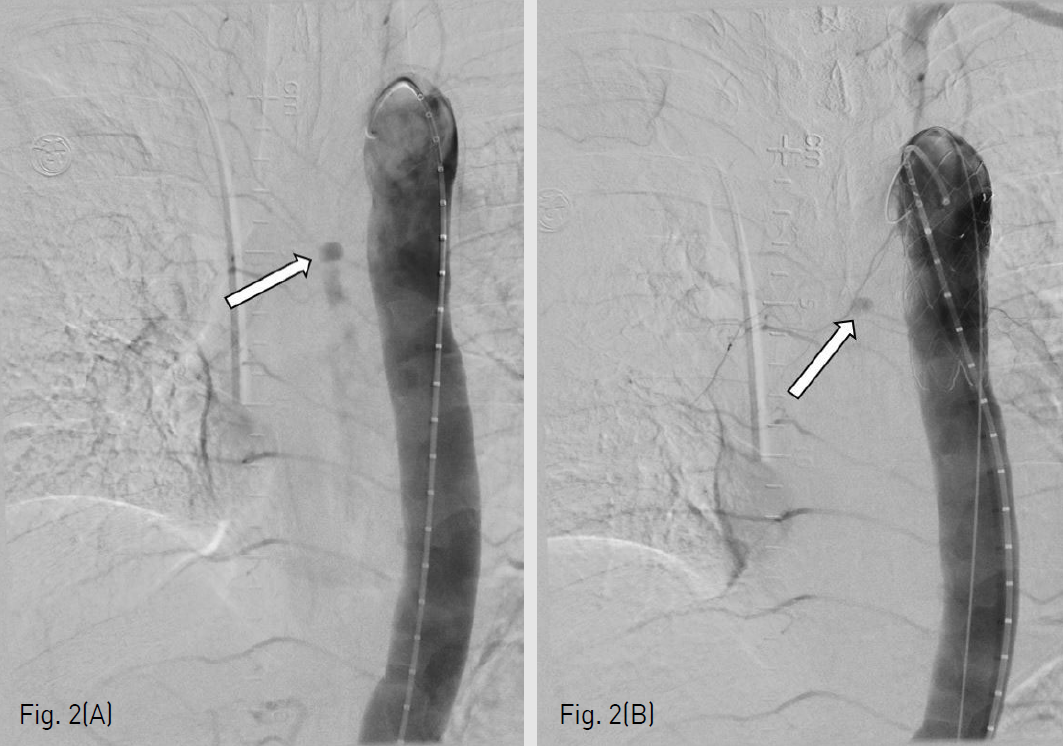

(B-C) On chest CT performed in emergency, pseudoaneurysm and aorto-esophageal fistula are seen in the posterior wall of the esophagus (arrows).

응급으로 시행한 조영증강 흉부 컴퓨터단층촬영에서 폐 우상엽의 중앙 부분과 내측에 공동을 동반한 폐렴이 있었다. 식도 중부의 후벽에 조영 증강되는 가성동맥류가 있었으며 대동맥에서 가성동맥류로 연결되는 대동맥식도루가 보였다 (Fig. 1B). 흉부 컴퓨터단층촬영에서 식도 내강으로의 조영제의 명확한 유출은 보이지않았으나, 해당 위치에서 출혈이 있는 것으로 판단하고 응급으로 혈관 내 치료가 의뢰되었다(Fig. 1C).